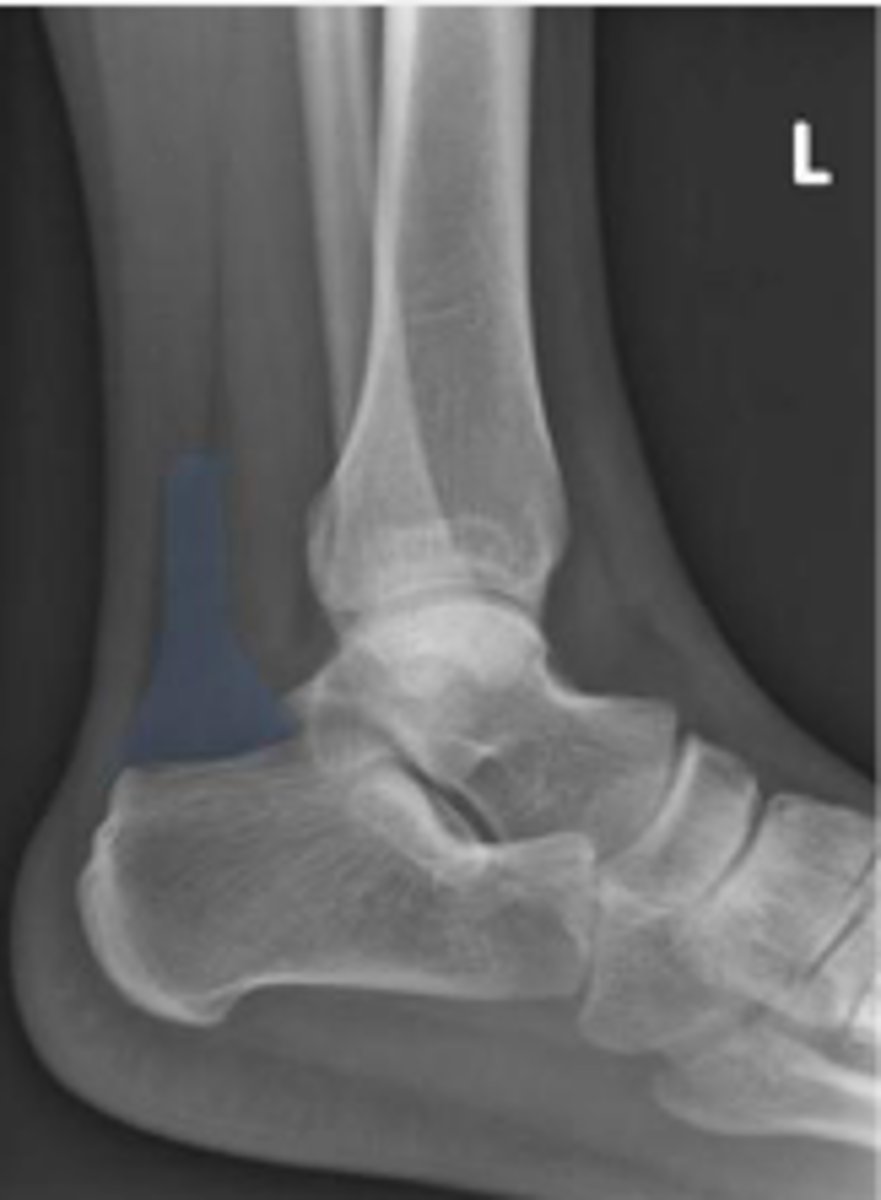

Talus of the left ankle

What space are the arrows pointing to?

Kager's fat pad of the left ankle

What is outlined?

Left fibula

What bone are the arrows pointing t